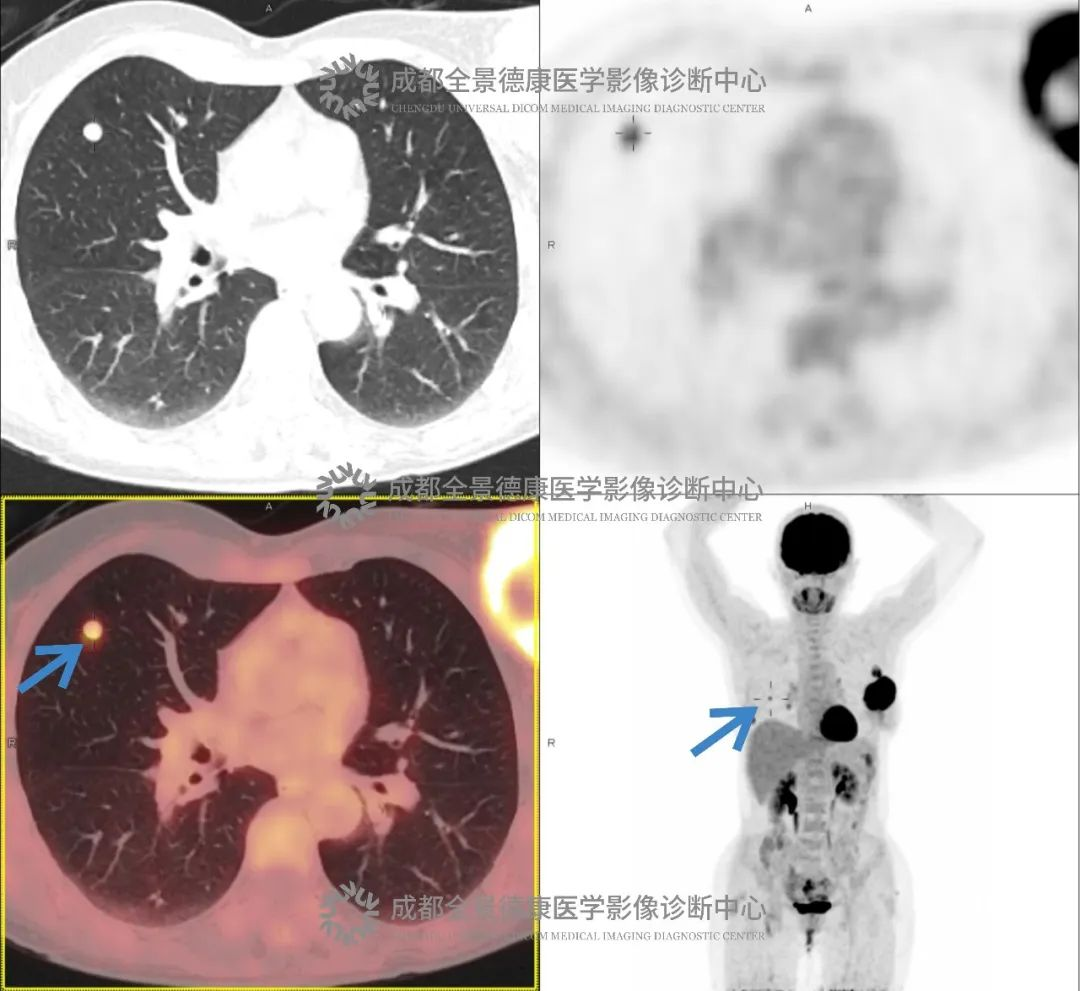

乳腺癌转移案例

夏女士(化名),4 个月前偶然发现左侧乳腺有包块,无疼痛、发热等症状。没太在意,但随着时间推移,包块越长越大,夏女士这才去医院,结果被诊断为「左侧乳腺癌」。为进一步评估全身转移情况,我们为夏女士进行了 PET/CT 检查。

影像:

左乳软组织肿块伴坏死,FDG 代谢活跃

诊断:

考虑乳腺癌,伴左乳头侵犯,左侧胸大肌受累可能;并伴:(1)左侧腋窝淋巴结转移;(2)双肺转移瘤。

夏女士平素未定期进行乳腺癌筛查,在乳腺发出「长出包块」的信号后也未引起重视,更遑论及时诊治,导致确诊时已出现淋巴结转移和肺转移,延误了治疗时机。